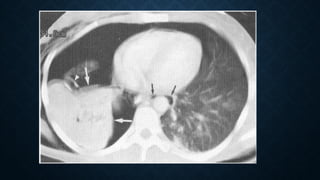

Lung contusion. Axial (a, b) and coronal

(c) CT images at lung window show

nodular opacities of ground-glass

opacity that do not respect the lung

boundaries of the right upper lobe. (A),

diffuse areas of ground-glass opacity in

the upper lobes bilaterally with

subpleural sparing (b) and multiple

areas of consolidation with air

bronchograms and small lacerations in

both lungs consistent with lung

contusions.